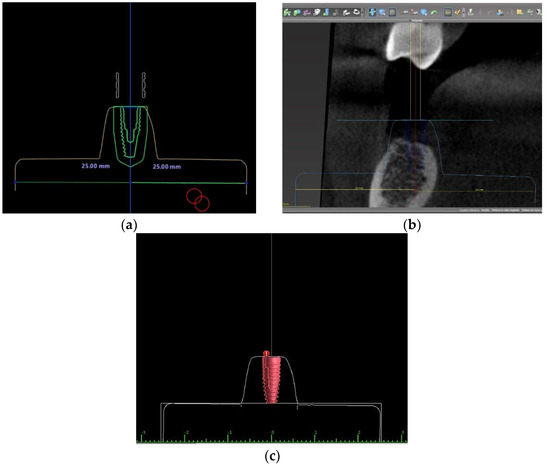

2.2. Implant Position Planning Procedure in Three Different Software Programs

2.3. Surgical Guide Design and Fabrication in Three Different Software Programs